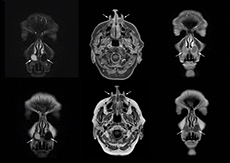

Dr. Heggelman raves about mDIXON TSE because it provides him an extra image series without having to add another scan. “With mDIXON TSE, we not only get a T2-weighted series, but we also get the T2 fat suppressed images ‘for free’ in the same scan. I feel much more confident with the homogeneous fat suppression that mDIXON TSE provides under virtually all conditions, even in this challenging anatomy. SPAIR and SPIR weren’t good enough due to the susceptibility problems in the air cavities, so that fat suppression was not homogeneous over the whole field of view. That made it difficult to see whether something was enhancing or the fat suppression was not good enough.”

“To me the most remarkable fact is that mDIXON TSE provides us T2-weighted images with and without fat suppression at the same time. In the past we needed two separate sequences for that, so it does save some time.”

Value of mDIXON TSE image quality

“The excellent image quality of mDIXON helps us a lot. We can, for instance, see the foramina in the skull base very well. Also our confidence in imaging of the facial nerve and the trigeminal nerve is highly improved. Visualizing these nerves properly used to be difficult because they run very close to the air cavities. However, it is very important to know if there are abnormalities or not. I’m very satisfied with the possibilities of mDIXON TSE.”